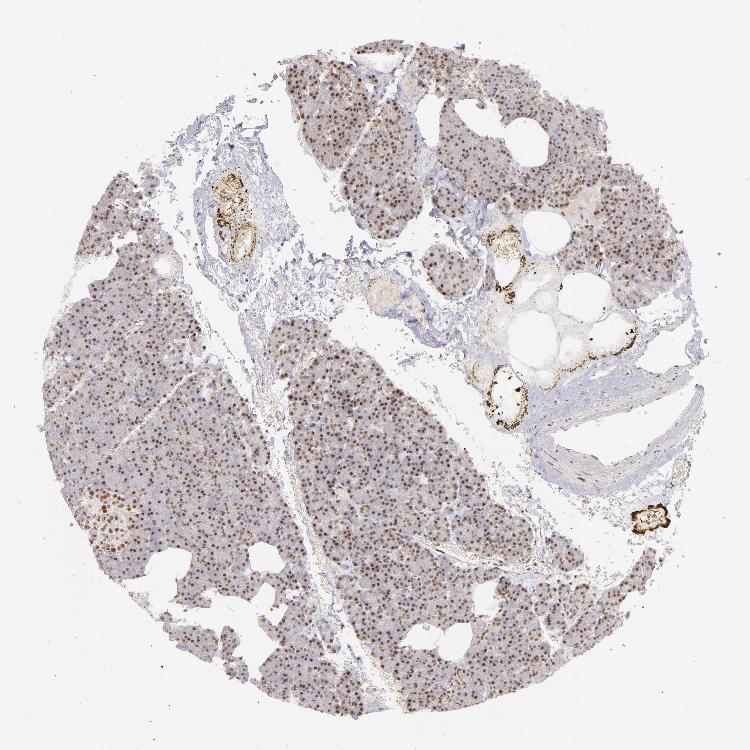

PANCREAS - Antibody stainingi

Antibody staining in the annotated cell types in the current human tissue is reported as not detected, low, medium, or high, based on conventional immunohistochemistry profiling in selected tissues. This score is based on the combination of the staining intensity and fraction of stained cells.

Each image is clickable and will lead to virtual microscopy that enables deeper exploration of all samples and also displays staining intensity scores, fraction scores and subcellular localization as well as patient and tissue information for each sample.

Antibody HPA001928

Exocrine glandular cells Medium

Pancreatic endocrine cells Medium